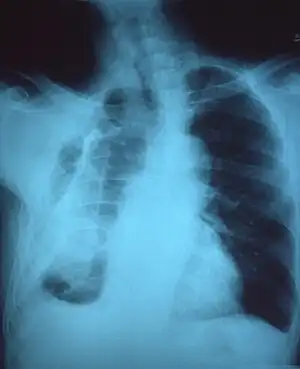

If a fibrothorax is severe, the thickening may restrict the lung on the affected side causing a loss of lung volume.[7] Additionally, the mediastinum may be physically shifted toward the affected side.[3] A reduction in the size of one side of the chest (hemithorax) on an X-ray or CT scan of the chest suggests chronic scarring.[6] Signs of the underlying disease causing the fibrothorax are also occasionally seen on the X-ray.[6] A CT scan may show features similar to those seen on a plain X-ray.[7] Lung function testing typically demonstrates findings consistent with restrictive lung disease.[6]

Chest radiograph displaying inhomogeneous opacification of the left half of the chest that is fibrothorax